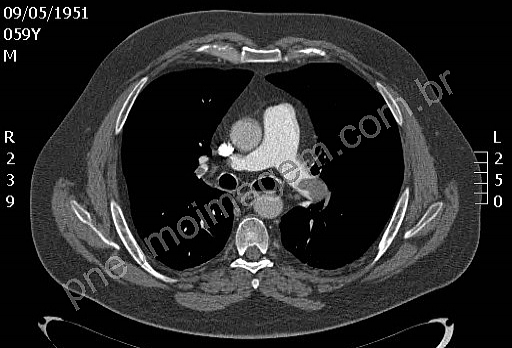

CASO CLÍNICO #44

Qual o principal diagnóstico ao se encontrar essa imagem em uma TC de tórax? Deixe os seus comentários abaixo!

What is the main diagnosis when you find this image on a chest CT scan? Give your comments below!